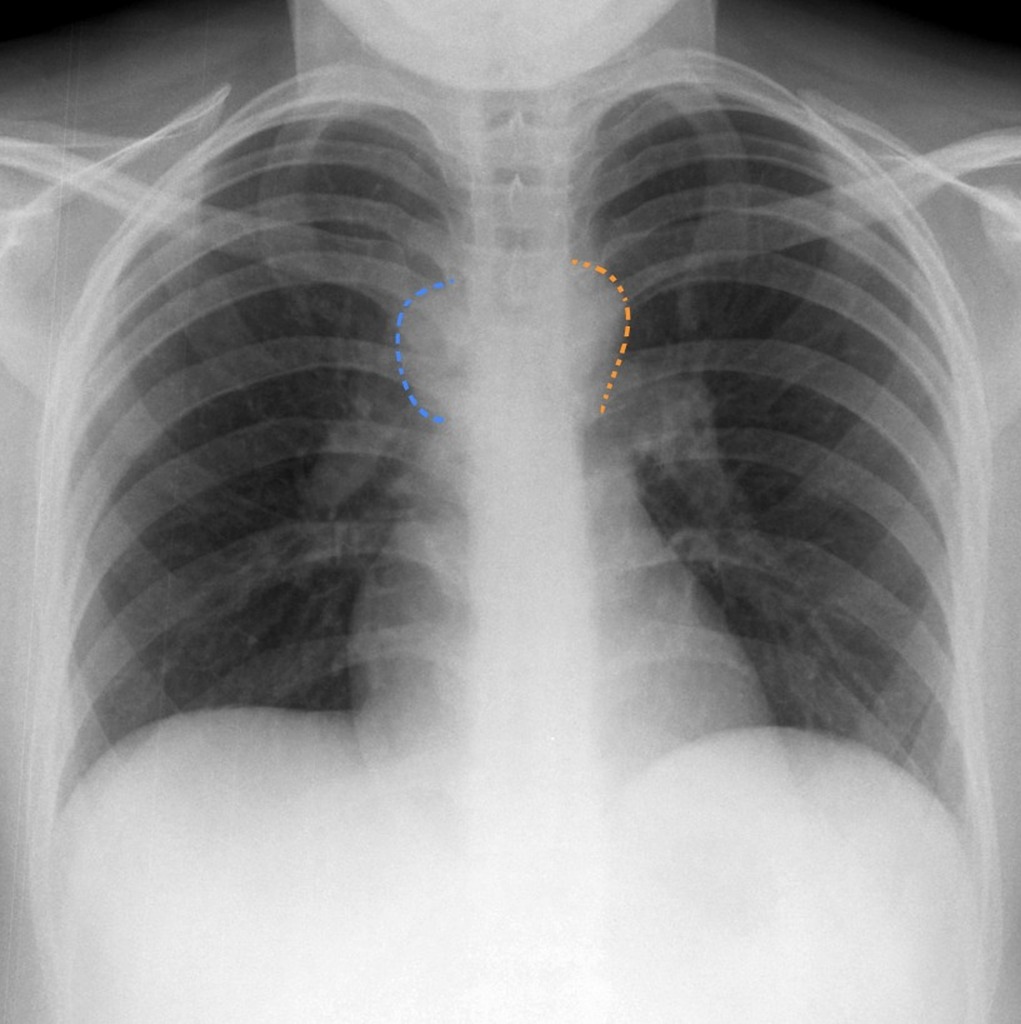

The location of precarinal lymph nodes in the body is the pericardial space. This space is present in the chest and is surrounded; by the ascending aorta, the left and right arteries, and tracheal bifurcation. In a few cases, lymph nodes may also falsify causing, intense pain in the pulmonary region. Calcifications in the lymph nodes result from prior granulomatous infections, particularly histoplasmosis and tuberculosis. However, it also includes some less common causes. Those less common causes include amyloidosis, sarcoidosis, silicosis, and secondary calcification to the lymphomas treatment. The patient exhibits precarinal lymph nodes enlargement with features that make them more specific. These clarifications involve multiple chains of lymph nodes that include some that present eggshell calcification.

Precarinal lymph nodes have a size of less than 10 mm in diameter. However, there are cases in which these lymph nodes enlarge themselves and exceed the usual size mentioned above. Now, what is the probability of that? According to one study, 60 of the 90 observed patients had normal-sized precarinal lymph nodes; less than 10 mm in diameter. What about the other 30 cases? The remaining 30 had enlarged precarinal nodes on CT scan, which were greater than 15 mm from the diameter point of view. Lymphadenopathy is visible in the precarinal lymph nodes that are present within the chest cavity around the lungs. The term used for the swollen lymph nodes in the chest is Mediastinal lymphadenopathy. These swollen lymph nodes appear specifically in the area between the lungs containing the heart, trachea, and esophagus or specifically the mediastinum. It is a sign of an underlying disease or infection.